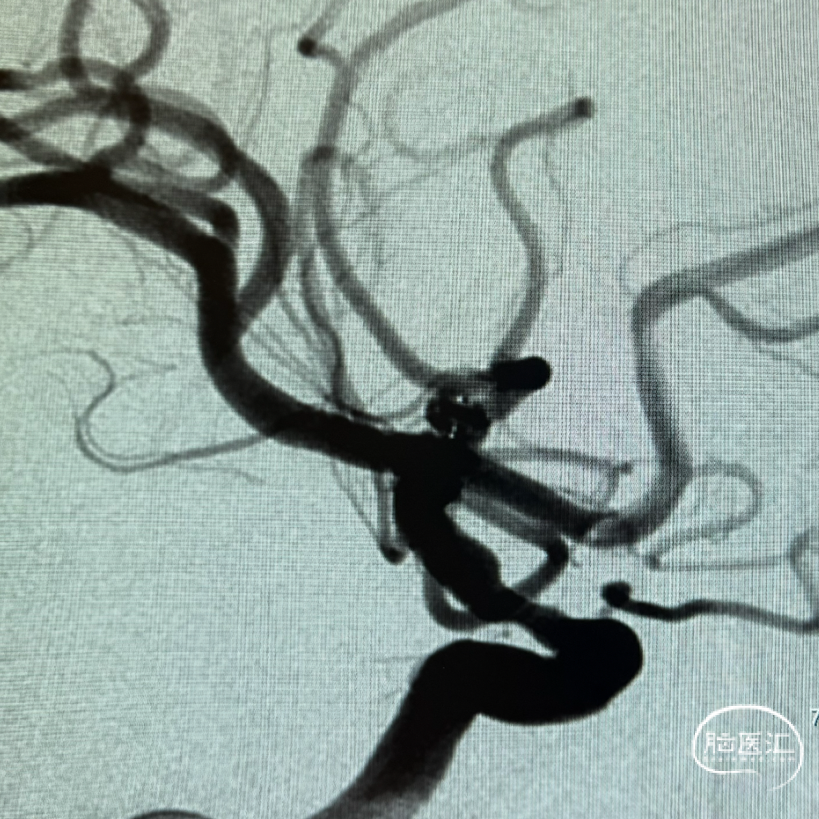

解脱后工作角度即刻造影,早额支及主干未受影响,动脉瘤内已可见血流分层。

术后三维重建及WEB™融合后图像,可见WEB™贴壁良好。

WEB™释放的实时评估:在成角部位,装置展开易受血流冲击影响。需通过多角度造影动态观察WEB™形态,重点确认瘤颈覆盖是否完全、尾端是否充分展开。本例通过反复调整,最终实现装置稳定贴壁,术后利用西门子自带多容积三维重建,分析扰流装置的位置,证实了技术操作的可靠性。